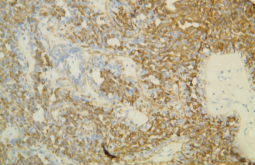

病理检查在确诊乳腺癌中扮演了重要角色。通过乳腺组织活检,医生可以确认癌症的类型和阶段,这些信息对治疗方案和预后判断至关重要。

图为乳腺癌组织活检病理切片